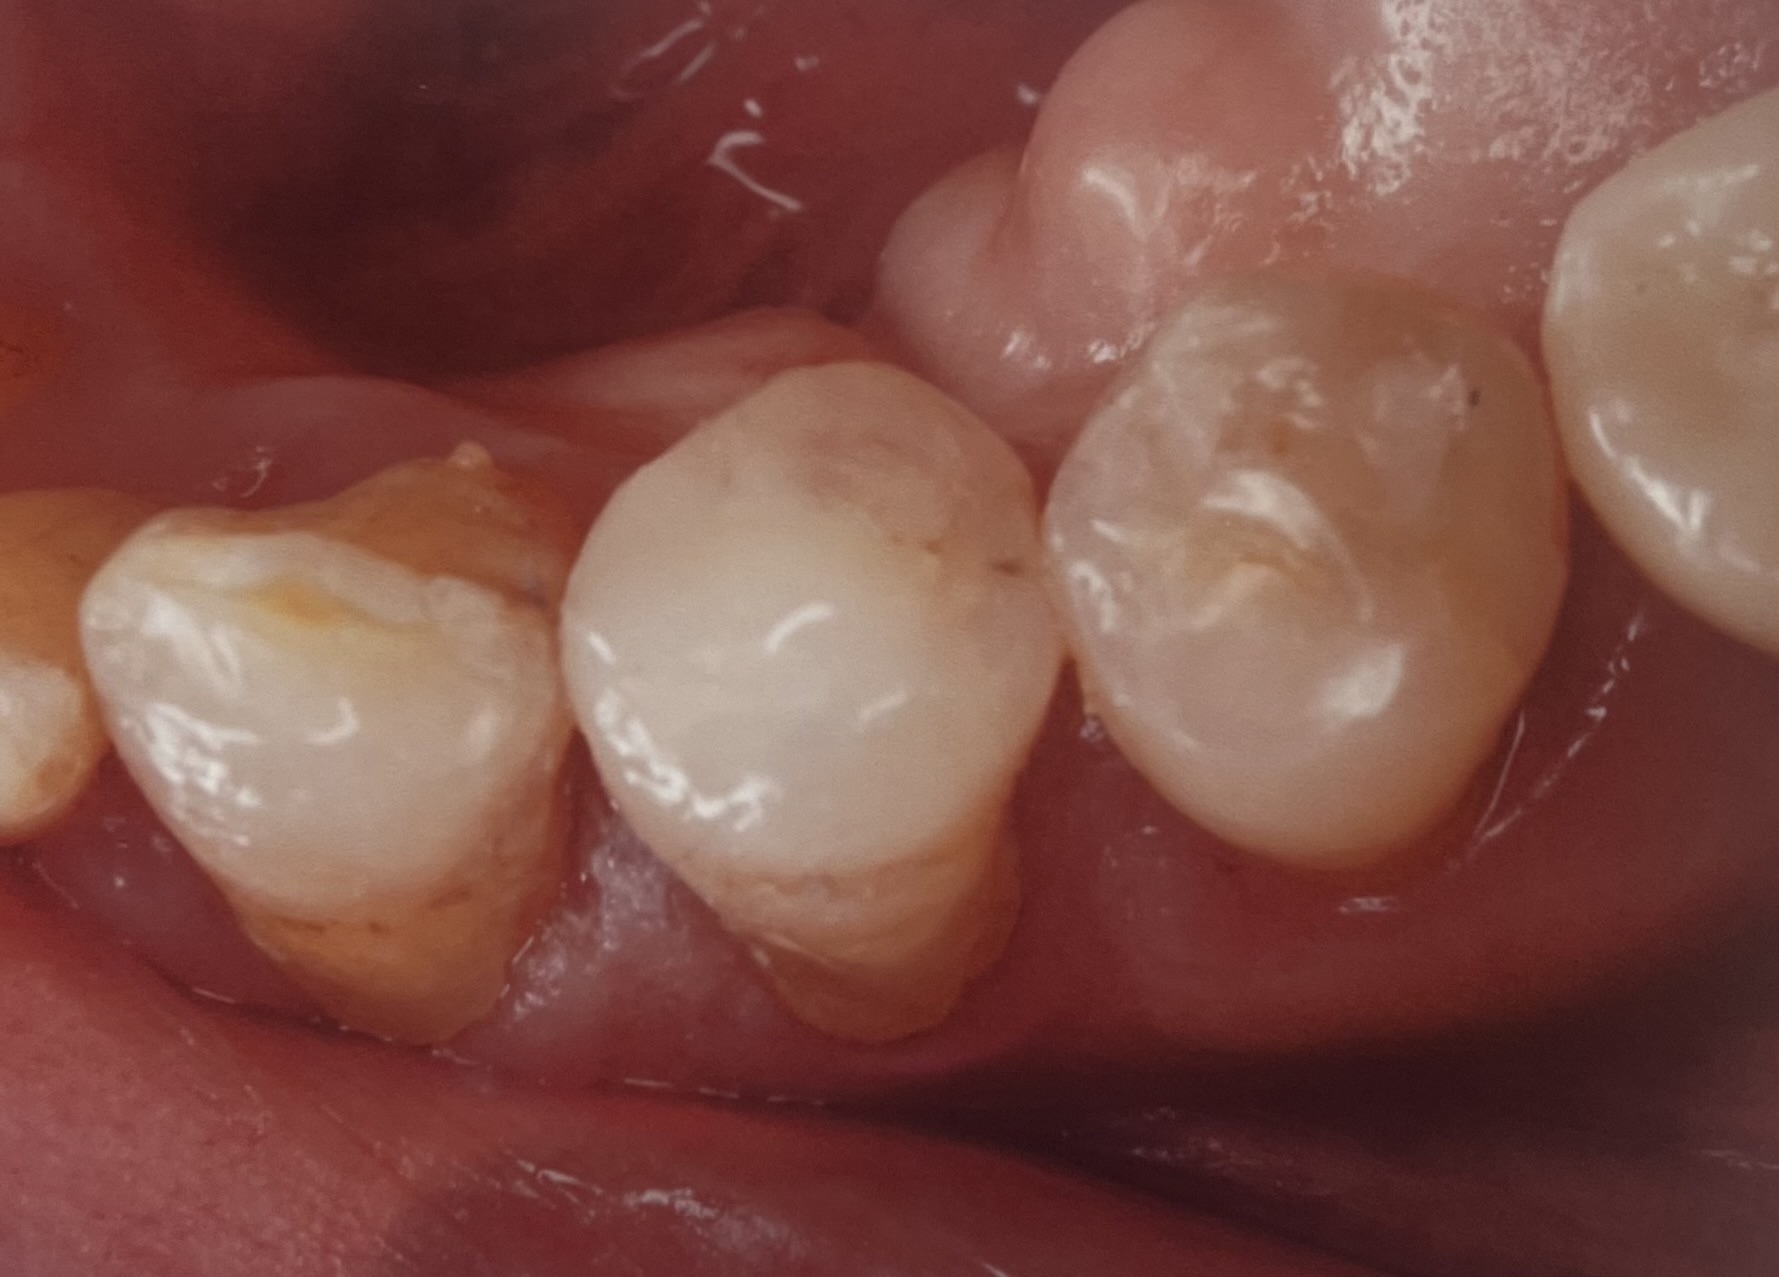

埼玉県志木市の佐藤デンタルクリニックです。今回は、部分的な銀歯を含む虫歯をぶぶんなセラミックで治療したものです。

ここには治療例を二つほど載せましたが、当院での治療数は、部分的なものだけで1500を超えています!そのなかで、銀歯のように外れたとかしみる、かけたなどの問題はほぼおきていません。

今回の治療は、エナミックという弾力があり、かけにくい噛みやすいセラミックを用いて行なっています、価格は、65000-80000円(税別)となります、虫歯の大きさなどによっては全体を覆うものも良いかと思いますが、歯の歯質を残したい方にはこの治療がおすすめです、